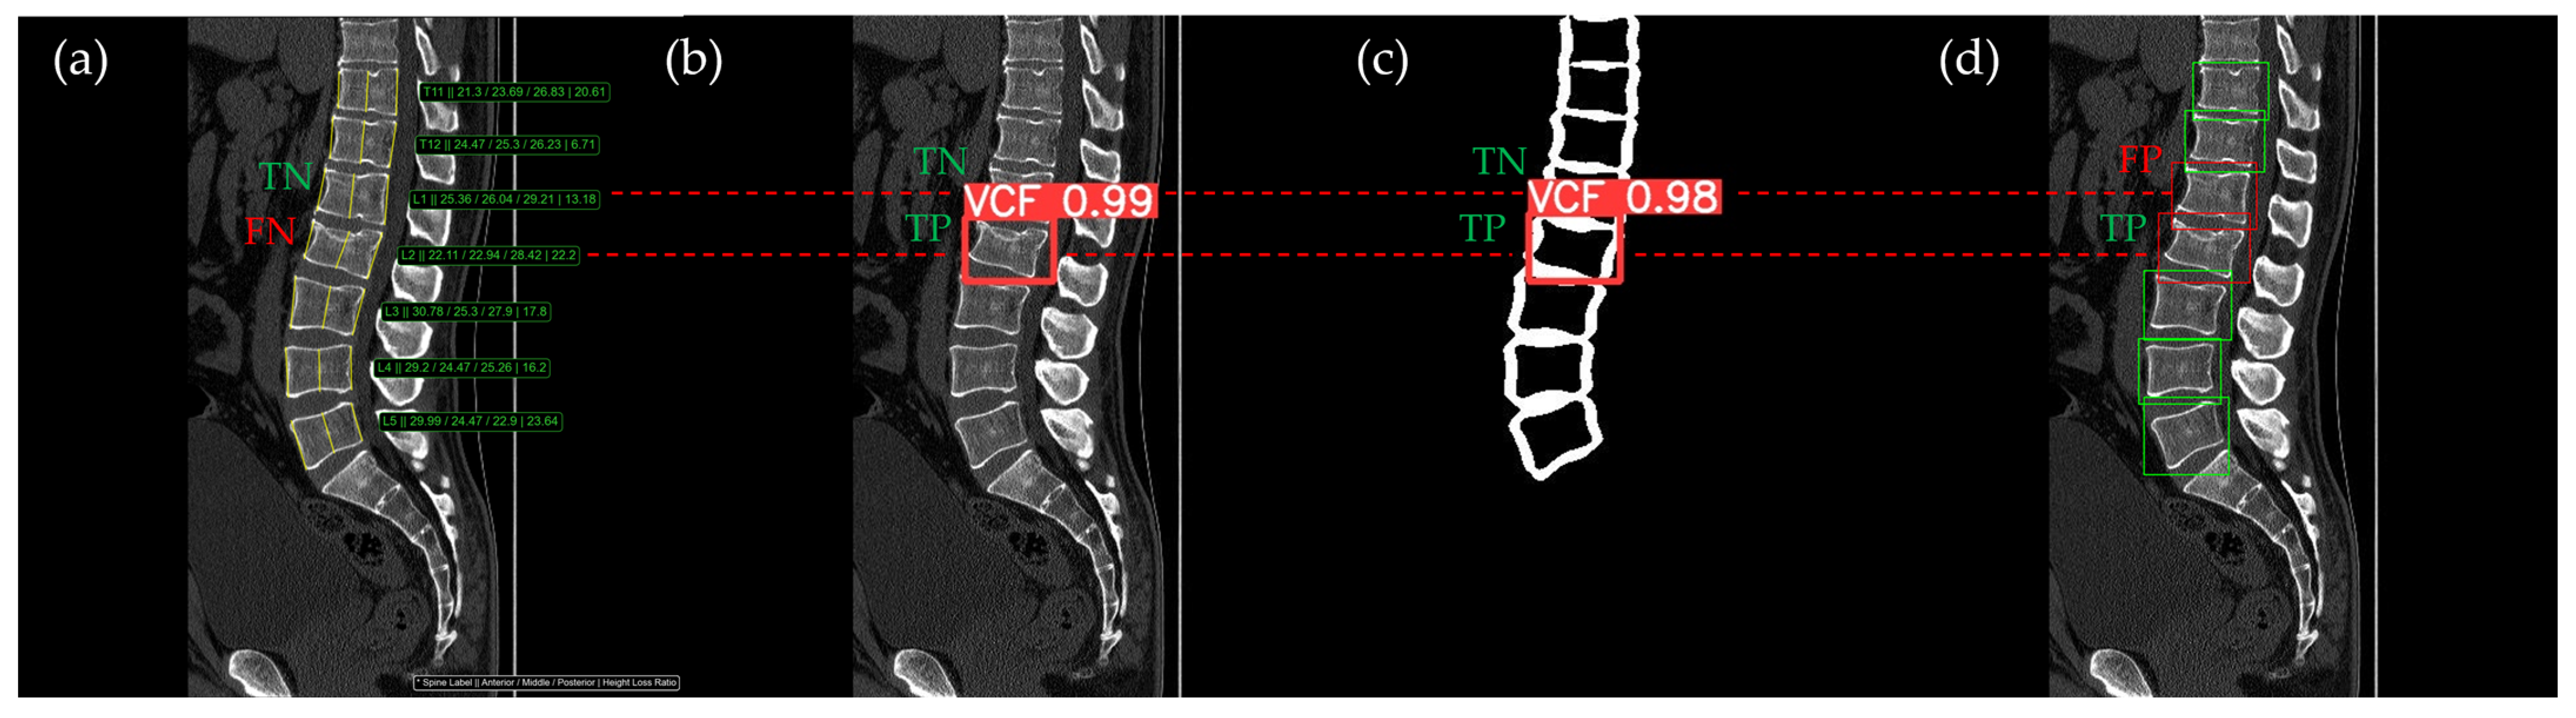

Figure 10, Figure 11, Figure 12, Figure 13 and Figure 14 illustrate typical examples of results for HLR, EEVD, TSVD_SD, and TSVD_DC in patients with acute VCFs. The results of applying different methodologies to the same patient image and identical slice locations were as follows. In the HLR results, each vertebra was marked with yellow solid lines indicating the height measurement lines for the anterior, middle, and posterior regions. The measured height values and HLR percentages were displayed on the right side of the image. If the HLR percentage ranged between 25% and 40%, it was highlighted in orange, while values of 40% or higher were highlighted in red. In the EEVD results, the VCF detection outputs were displayed along with their respective confidence scores based on the input patient images. For the TSVD_SD results, after performing spine segmentation, the model extracted only the spine contour, and the VCF detection results with their corresponding confidence scores were presented. In the TSVD_DC results, bounding boxes were generated for each vertebral body, with normal vertebrae represented in green and vertebrae identified as VCFs displayed in red.

Figure 13.

The VCF detection results from four different methods. (a) HLR, (b) EEVD, (c) TSVD_SD, and (d) TSVD_DC. The acute VCF, as confirmed by the radiologist, was located at the L2 level. TP, TN, FP, and FN were marked at the same level with a red dotted line. The HLR was low at L2, which was the reason for the FN in (a). The L1 vertebra was misclassified as VCF by TSVD_DC.

In Figure 13, the L1 vertebra was normal, whereas a VCF was present at the L2 level. This patient exhibited irregular cortical endplate appearances from T11 to L2. Radiological evaluation concluded that there was an acute VCF only at the L2 level, which the HLR method failed to detect. However, all convolutional neural network (CNN)-based methods—EEVD, TSVD_SD, and TSVD_DC—successfully detected the VCF at L2 by extracting and analyzing specific features of spinal images. In TSVD_DC, there was an additional FP, as the model incorrectly identified a VCF at L1.